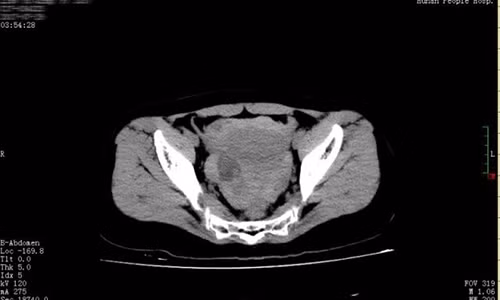

| Bản chụp CT phát hiện ra rằng Hiểu Khánh có một lượng máu lớn và chất lỏng trong ổ bụng và vùng chậu. Ảnh: Xiaoxiang Morning Post. |

Bác sĩ Huang Mei thuộc Bệnh viện Nhân dân tỉnh Hồ Nam (Trung Quốc) cho biết Hiểu Khánh không mang thai, bản chụp CT phát hiện ra cô có một lượng máu lớn và chất lỏng trong ổ bụng và vùng chậu.